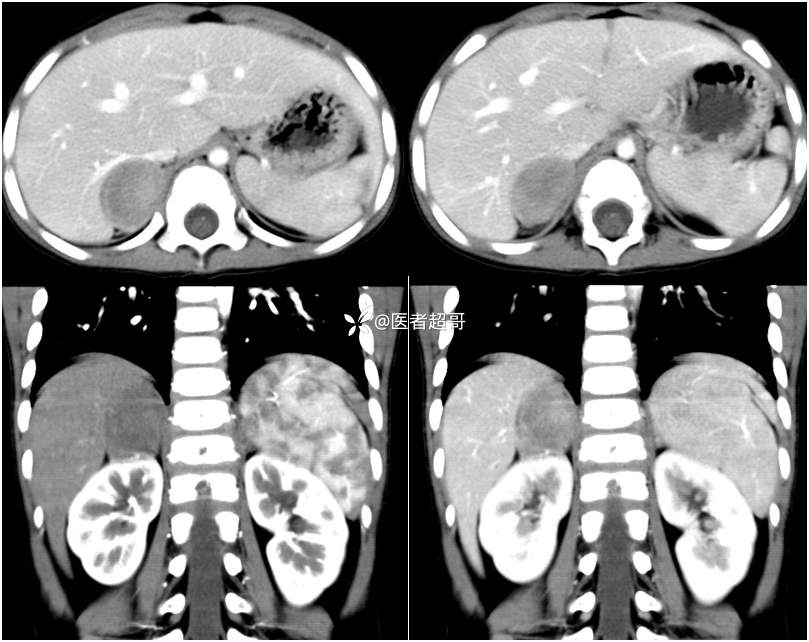

病例【影诊笔记713】男,3岁,发现肝占位入院?请诊断分析!